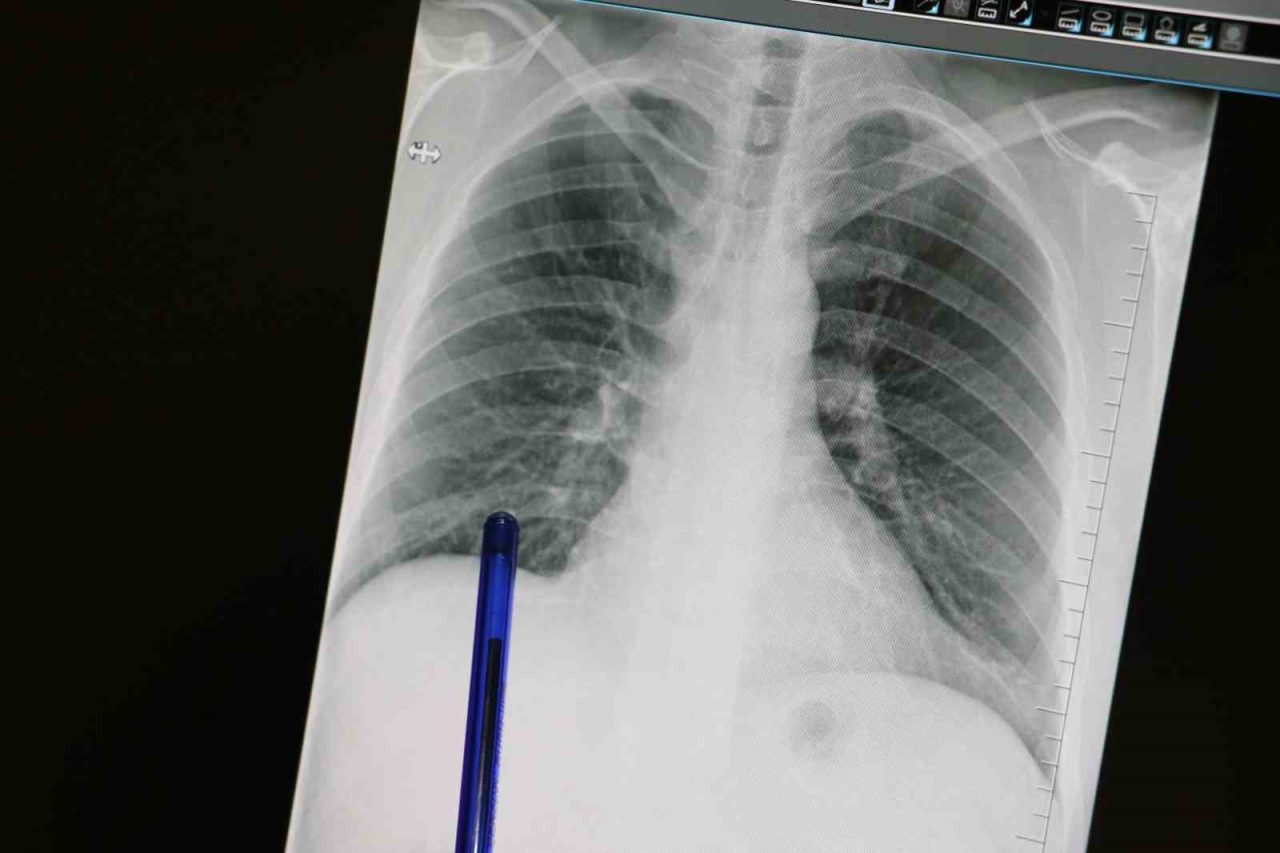

Kasım ayı, Türkiye’de akciğer kanserine dikkat çekmek ve erken tanının önemini vurgulamak amacıyla ‘Akciğer Kanseri Farkındalık Ayı’ olarak kabul ediliyor. Akciğer kanseri ise akciğer dokusundaki hücrelerin kontrolsüz çoğalmasıyla oluşan ve diğer organlara yayılabilen ciddi bir hastalık olarak biliniyor. Genellikle erken evrelerde belirti vermediği için geç fark ediliyor ve bu durumda tedavi şansını azaltıyor. En önemli risk faktörü sigara kullanımı olsa da, sigara içmeyen kişilerde de bu hastalık görülebiliyor. Pasif içicilik, hava kirliliği, genetik yatkınlık ve bazı kimyasal maddelere uzun süreli temas ileri yaşta akciğer kanseri riskini artıran diğer etkenler arasında bulunuyor. Konuya ilişkin açıklamalarda bulunan Medicana Sivas Hastanesi Göğüs Hastalıkları Uzmanı Dr. Büşra Yayla Yerlikaya, öksürük ve balgam çıkarma gibi basit görünen semptomların kanserin belirtisi olabileceğini söyleyerek, “Bu hastalık, hem dünyada hem de ülkemizde kansere bağlı ölümlerin en sık nedenidir. Ne yazık ki genellikle erken evrede belirti vermediği için geç tanı alabilmekte ve bu da tedavi şansının azalmasına sebep olabilmektedir” dedi.

Akciğer kanserinin büyük bir kısmını sigara ile ilişkili olduğunu söyleyen Büşra Yayla Yerlikaya, “Bu hastalık, hem dünyada hem de ülkemizde kansere bağlı ölümlerin en sık nedenidir. Ne yazık ki genellikle erken evrede belirti vermediği için geç tanı alabilmekte ve bu da tedavi şansının azalmasına sebep olabilmektedir. Akciğer kanserlerinin büyük kısmı, neredeyse yüzde 85-90 kadarı bilindiği üzere sigarayla ilişkilidir. Günde içilen sigara sayısı ve kullanım süresi arttıkça risk de katlanarak artar. Ancak hiç sigara içmeyenlerde de pasif içicilik de en az aktif içicilik kadar önemli bir faktördür. Elektronik sigaralar ya da ısıtılmış tütün ürünleri de sanıldığı gibi güvenli değildir. Nikotin içerdikleri için bağımlılığı sürdürürler ve ekstra pek çok kimyasal daha içerirler. Uzun vadeli zararları henüz tam olarak bilinmemektedir” dedi.

Özellikle sigara içen bireyde öksürük gibi belirtiler varsa bir uzman tarafından değerlendirilmesi gerektiğini belirten, “Akciğer kanserinin en sık belirtileri ise uzun süren öksürük, balgamda kan, nefes darlığı, kilo kaybı ve göğüs ağrısıdır. Özellikle sigara içen birinde yeni başlayan ya da karakteri değişen öksürük varsa mutlaka bir göğüs hastalıkları uzmanı tarafından değerlendirilmelidir. Erken tanı her kanser türünde olduğu gibi akciğer kanserinde de hayat kurtarır. 50 yaş üzeri ve uzun süre özellikle 20 paket yıl ve daha fazla sigara içmiş kişilerde düşük doz tomografi ile tarama yapılması, hastalığın erken evrede erken tanı sağlar ve tedavi şansını ciddi şekilde artırır. Sigarayı bırakmak her yaşta faydalıdır. Bıraktıktan sonraki on yıl içinde akciğer kanseri riski büyük oranda azalır. Çalışmalar 10 yıl sonra yüzde 50, 15 yıl sonra ise yüzde 90’a kadar akciğer kanseri riskinin azaldığını göstermiştir. Sigara içen bireylerde sabahları balgam ve öksürükler mevcut oluyor. Bu durumlarda balgamın karakter değiştirmesi ve artması önemli bir belirti olabiliyor” diye konuştu.